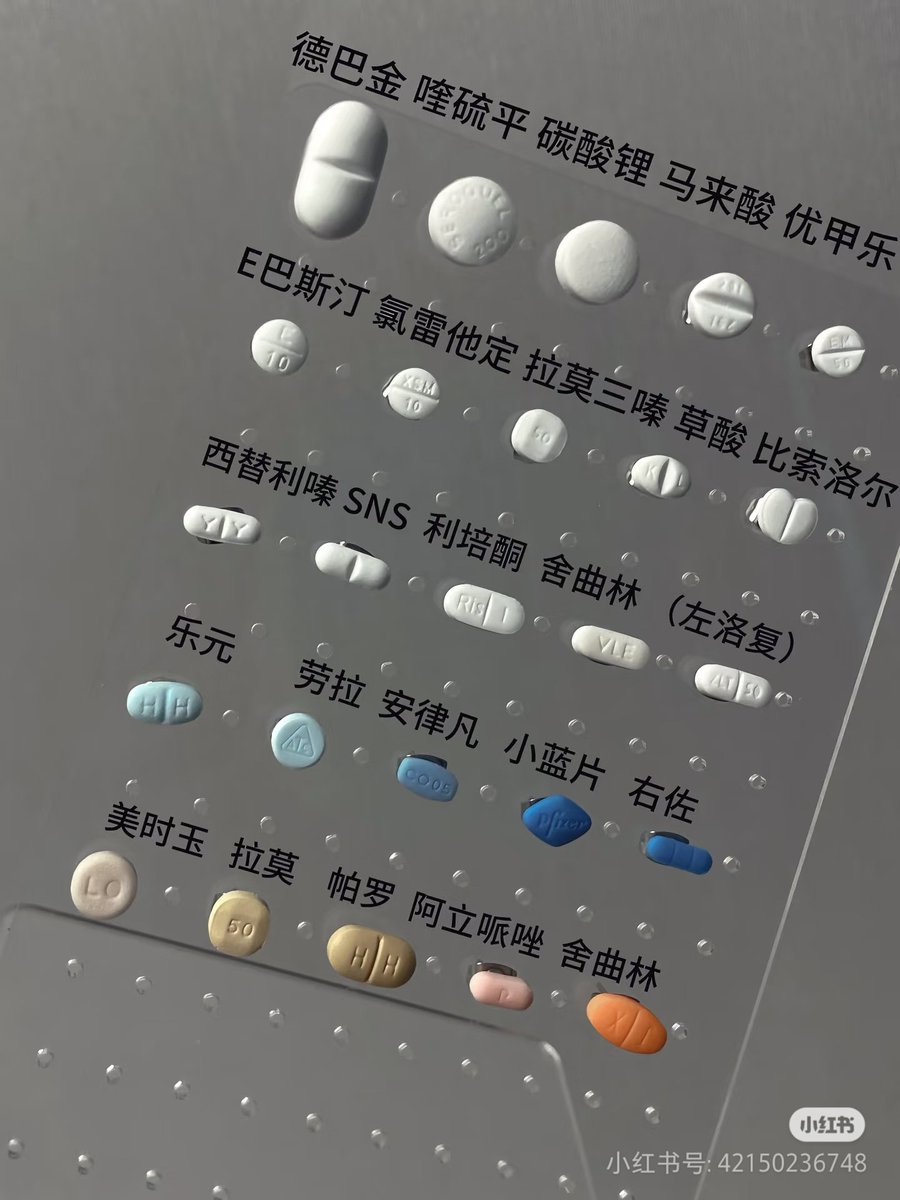

对于药物过量引起的中枢神经系统副作用,有一些不常见或常见的药物来控制症状。

评论区欢迎补充 https://t.co/7S4tGVDEM5